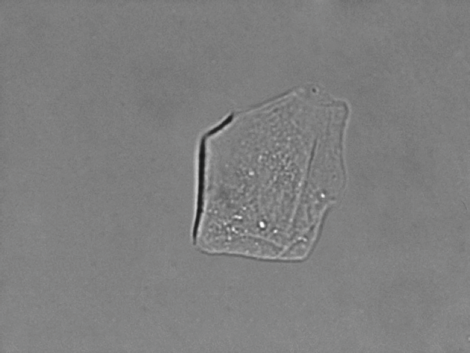

Ejemplos de imágenes

Hasta 96 imágenes están incluidas con cada ejecución de la muestra, con 6 imágenes automáticamente seleccionadas para su revisión. O elija y seleccione cuáles imágenes resaltar: todas se guardan en la base de datos con un solo clic.

Todas las imágenes son representativas de un campo de visión con objetivo de 40x. Las imágenes se toman del VETSCAN SA.

Cristales de estruvita